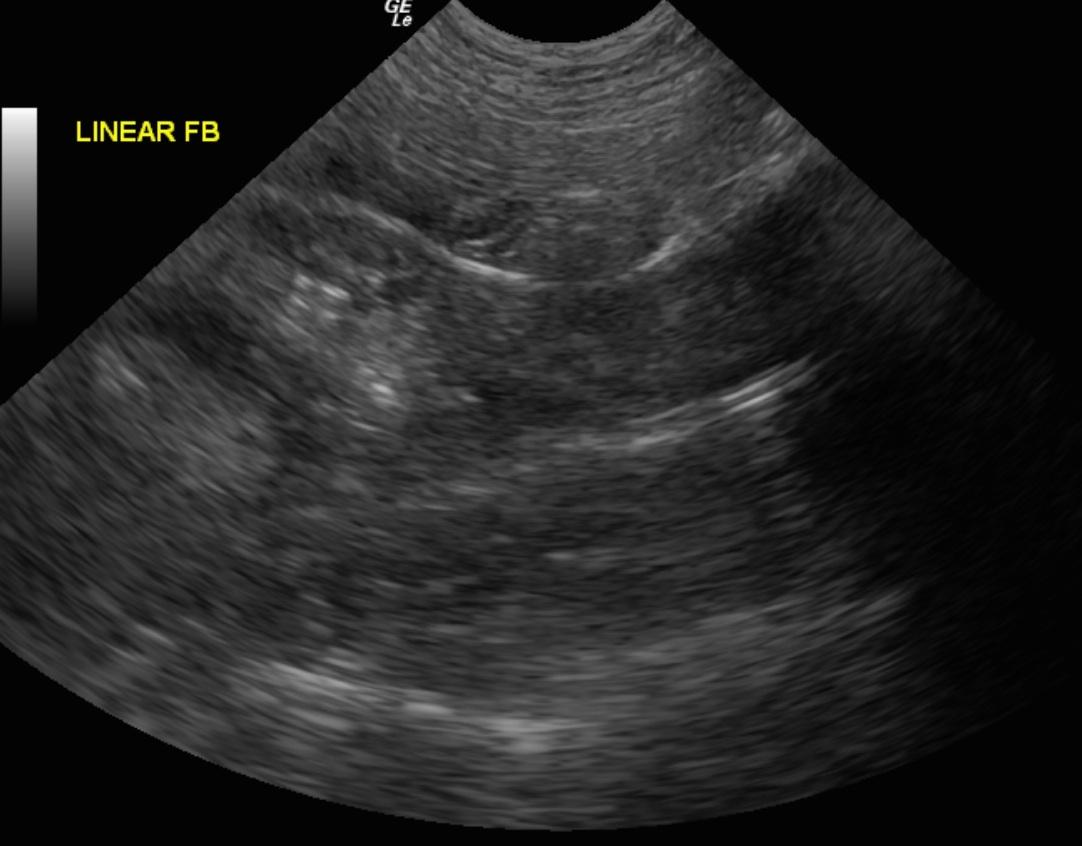

An 8-month old MN Cockapoo dog was presented with a history of vomiting, diarrhea, anorexia, lethargy, and painful abdomen. Leukocytosis was present on CBC, whereas serum biochemistry panel was within normal limits.